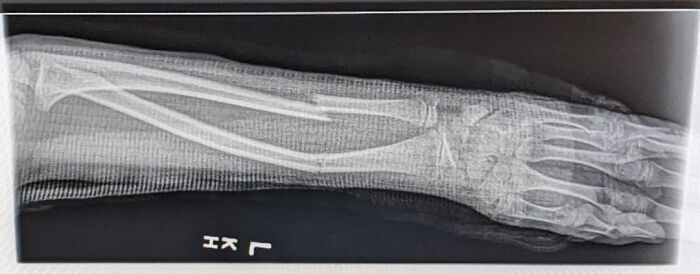

Update: Reddit Called My Scoliosis! Doctor Confirmed I’m Getting Physio Tomorrow